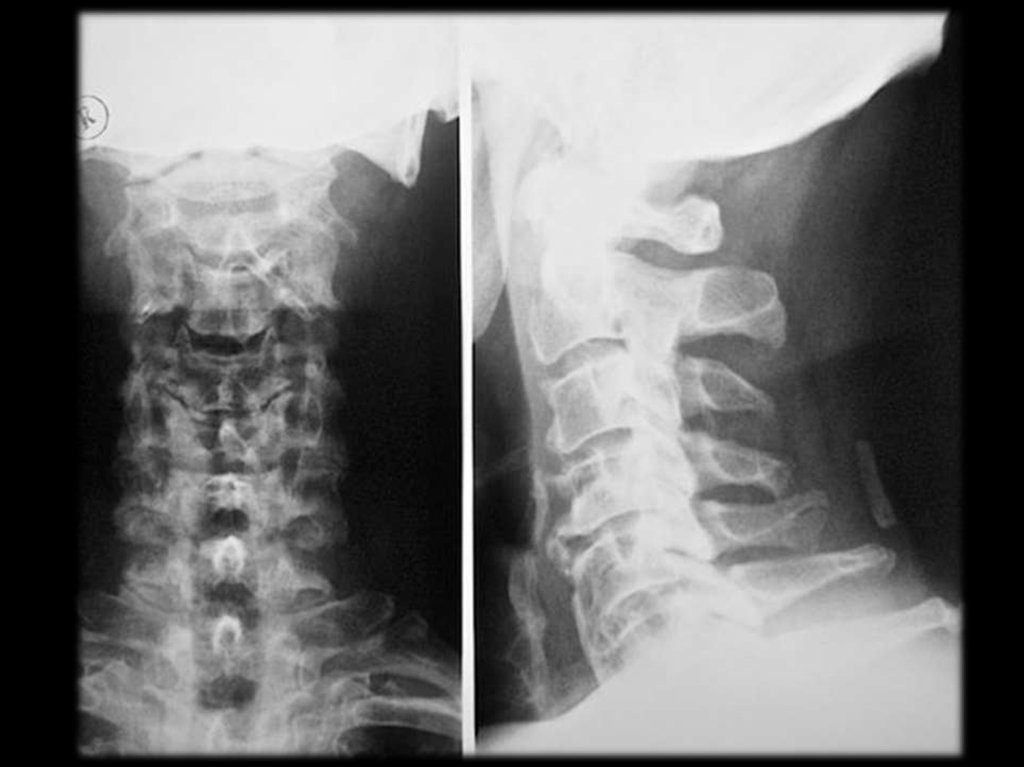

В шейном отделе клинически наиболее значимы

остеофиты

и

артрозы

унковертебральных

сочленений.

остеофиты и артрозы унковертебральных сочленений.